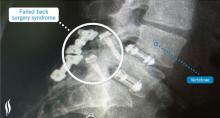

Actualité publiée il y a 9 années 1 semaineFIBROMYALGIE et CHIRURGIE ORTHOPÉDIQUE : Un couple infernal